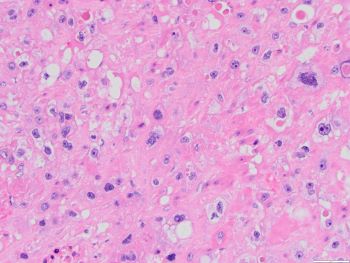

A 34-year-old female with abdominal pain, fever, chills. CT showed uterine rupture with abscess or mass and peritonitis. Urinary hCG (-). No other past medical history. An LUS-centered transmural mass noted, with tumor cells GATA3 (+), p16 weak patchy, desmin (-); H&E shown.

The patient’s last pregnancy was in 2013. Her PAP test and gynecologic exams have been normal. An abdominal hysterectomy with bilateral salpingo-oophorectomy was performed. Sections showed a relatively well demarcated neoplasm with polygonal cells in a predominant diffuse pattern, with moderate amount of eosinophilic or clear cytoplasm. Most of the cells had distinct cell borders, and moderate nuclear atypia with vesicular chromatin and prominent nucleoli. Areas of geographic necrosis were seen with islands of viable neoplastic cells, sometimes surrounding blood vessels. Focally the tumor cells colonized the endocervical epithelium. The tumor cells were positive for cytokeratin CAM5.2, GATA-3, inhibin, p63, and negative for CK5/6, SMA, desmin, with weak, noncontinuous staining with p16 and a Ki-67 proliferation index of about 20%. The clinical history, morphologic features and immunophenotype in this case are consistent with an epithelioid trophoblastic tumor.

A squamous cell carcinoma is less likely given her history of normal PAP tests, the pattern of p16 staining, and positivity for inhibin and GATA-3. The strong and diffuse positivity for cytokeratin, negativity for desmin and SMA, along with the remaining staining pattern, argues against a leiomyosarcoma. A placental site trophoblastic tumor is in the differential diagnosis, but the lower uterine segment location of the tumor, architectural and cytological features, and positivity for p63 favor an epithelioid trophoblastic tumor. The monomorphic tumor cell population with a Ki-67 of about 20% do not support a choriocarcinoma.